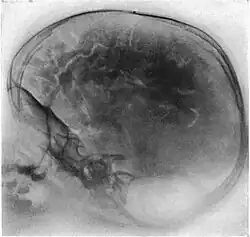

Pneumoencefalografia (wentrykulografia powietrzna, ang. pneumoencephalography) – inwazyjny zabieg diagnostyczny ośrodkowego układu nerwowego, polegający na zastąpieniu części płynu mózgowo-rdzeniowego powietrzem, tlenem albo helem wprowadzonym przez nakłucie do kanału rdzenia kręgowego i wykonaniu zdjęcia rentgenowskiego głowy. Gazy kontrastują dobrze układ komorowy mózgowia, co pozwalało uzyskać przyżyciowy obraz komór mózgowia zanim wynaleziono i udoskonalono inne techniki diagnostyki obrazowej układu nerwowego, TK i MRI. Metodę stosowano szeroko w połowie XX wieku, zarzucono niemal całkowicie w latach 80. Przeprowadzenie badania było niezmiernie bolesne dla pacjenta i obarczone poważnym ryzykiem powikłań. Wcześniej stosowaną metodą z której rozwinęła się pneumoencefalografia była wentrykulografia, w której powietrze wprowadzano do układu komorowego przez otwory wiercone w czaszce.